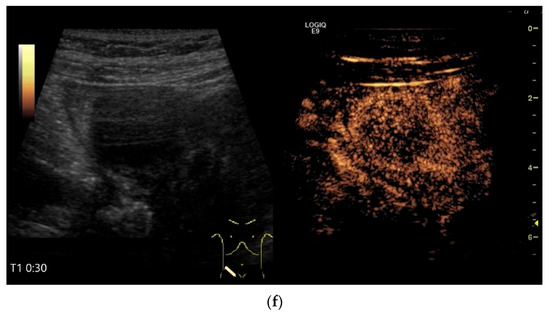

The only US description of an ileal IFP is as a clearly defined “target-like” lesion, which led to ileo-ileal intussusception [130] (Figure 13).

Figure 13.

Inflammatory fibroid tumor (Vanek’s tumor). In cases of unclear occult gastrointestinal bleeding, a smooth-edged oval hypoechoic mass measuring up to 30 mm in size can be seen in the terminal ileum. Examination with the abdominal sector transducer 1–5 MHz (a) and linear transducer 2–9 MHz (b). In power Doppler, a feeding vessel (c) and macro vessels in the mass (d) are visible. In CEUS with 2.4 mL SonoVue using a 9 MHz linear transducer, hyperenhancement is only visible at the edge in the arterial phase. Few vascular signals are visible in the lesion (e). The tumor remains hypoenhanced (f).